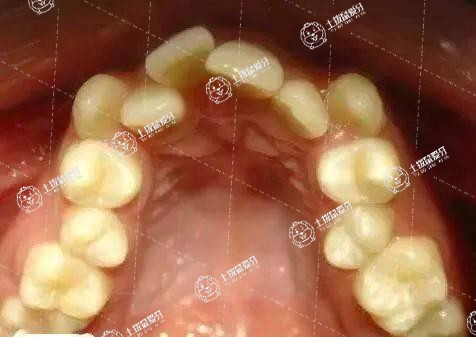

牙齒擁擠矯正需要的價(jià)錢(qián)一般是10000-80000元左右,這個(gè)價(jià)錢(qián)要根據(jù)選擇的矯正方式來(lái)看。矯正牙齒擁擠的方式有傳統(tǒng)鋼絲矯正以及隱形矯正和美容冠矯正等,選擇不同的矯正方式,操作難度不同,做出來(lái)的效果也不一樣,所以?xún)r(jià)錢(qián)上會(huì)有差別。如果選擇隱形牙套進(jìn)行牙齒矯正,那么價(jià)格就略貴,大概在80000元左右,如果選擇傳統(tǒng)的鋼絲牙套進(jìn)行牙齒矯正,價(jià)格就要便宜一些,大概在10000元左右。矯正后要注意口腔衛(wèi)生,禁止食用堅(jiān)硬的食物,例如硬殼、骨類(lèi)食品,飯后要漱口。

牙列擁擠的矯治步驟和大多數(shù)錯(cuò)(牙合)畸形的矯治步驟是一樣的,主要包括前期的準(zhǔn)備過(guò)程。要先檢查口內(nèi)情況,并拍攝相應(yīng)X光片,了解牙齒在骨頭里的情況以及上下頜骨的情況,然后進(jìn)行取模、拍照。